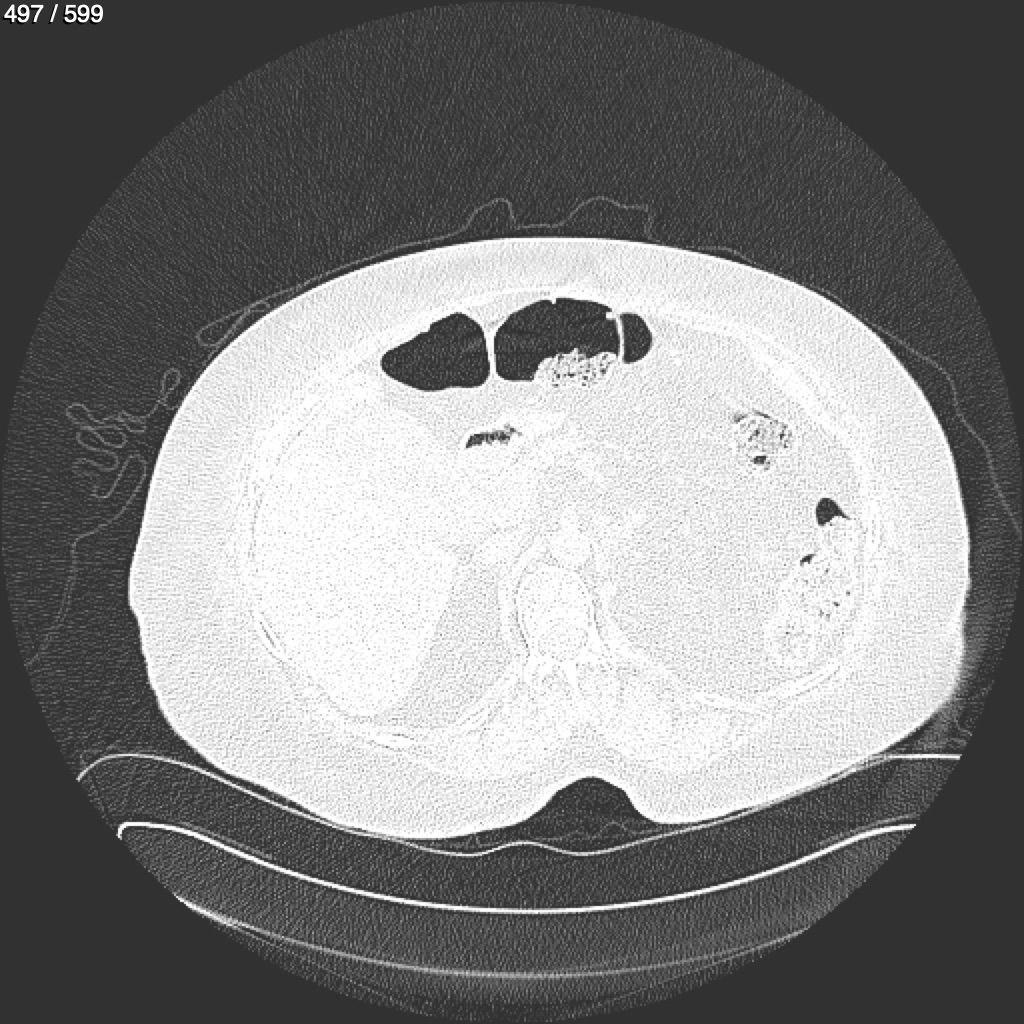

Home G​l​o​r​i​a​ ​G​l​a​d​y​s​ ​B​e​a​s​l​e​y​ ​-​ ​T​ó​r​a​x​ ​T​o​r​a​x​_​S​i​m​p​l​e​ ​(​A​d​u​l​t​o​)